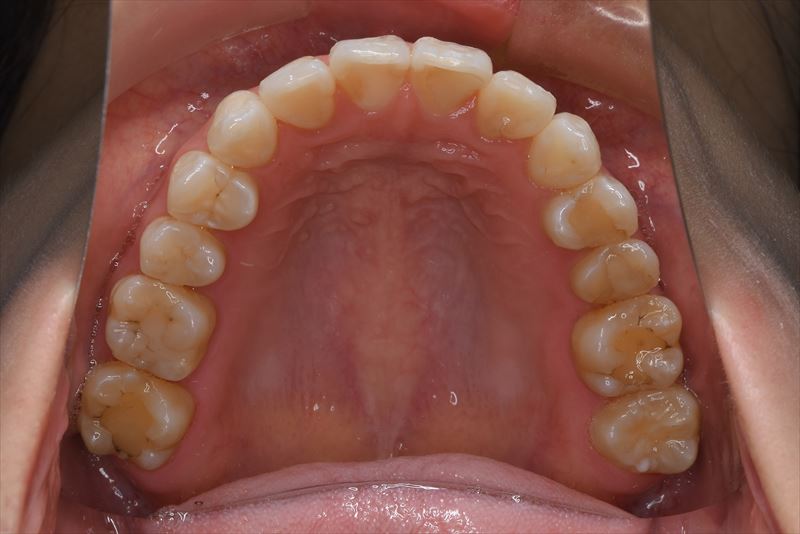

治療中

- 両側2番クロスバイト、叢生、上顎左側6番根尖病巣

- マルチブラケット装置、アンカースクリュー

- 上顎左側6番は失活歯で根尖病巣を認めたため抜歯し、上顎左側8番を代わりに使用することとしました。アンカースクリューを使用することにより、健康な歯を抜歯せず臼歯の遠心移動で叢生の改善できました。治療期間が短かく良好な咬合を獲得できました。